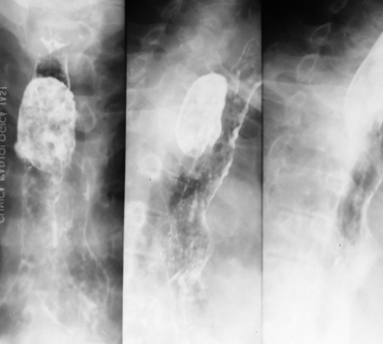

Neoplasm malign gastric vegetant